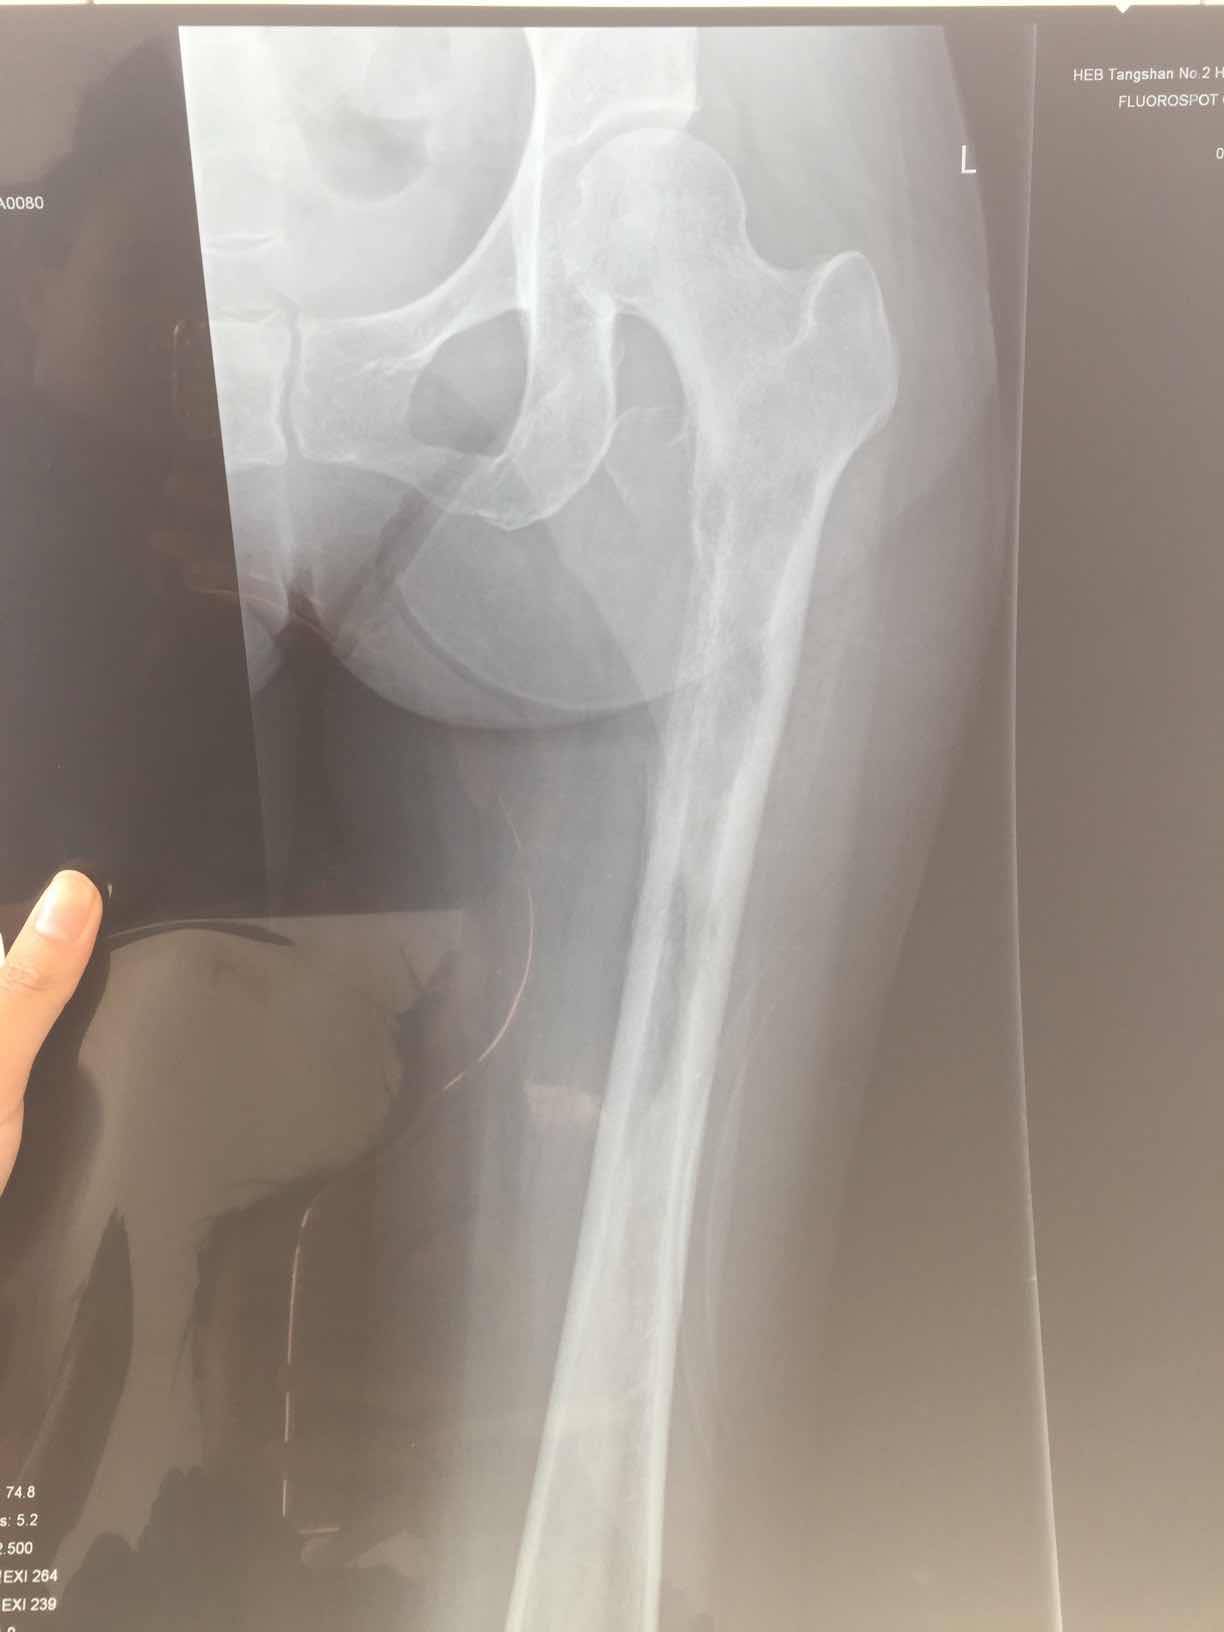

这是第一次确诊是拍的腿部ct,因为是腿疼才去检查,直接去的骨科医院,没想到确是转移,主要是左大腿疼痛,在家以为是腰间盘卧床躺了3月,期间就第三个月疼痛无比,刚开始两月还好,也能行走,就是腿疼,尽量不走,等再去医院检查的当天还把左大腿根掰了下,可能造成了骨裂,图片为最后一张图画圈的那里,打了两次骨转针。吃了一个月易瑞沙,腿已经不疼了,但是由于骨裂那块,还是卧床不让行走,医生也说让静养,怕骨折。我想问问大家有没有这方面的,我家这个情况该怎么办。还有机会在站起来行走吗,目前左腿肌肉萎缩的还比较厉害,拜托大家。